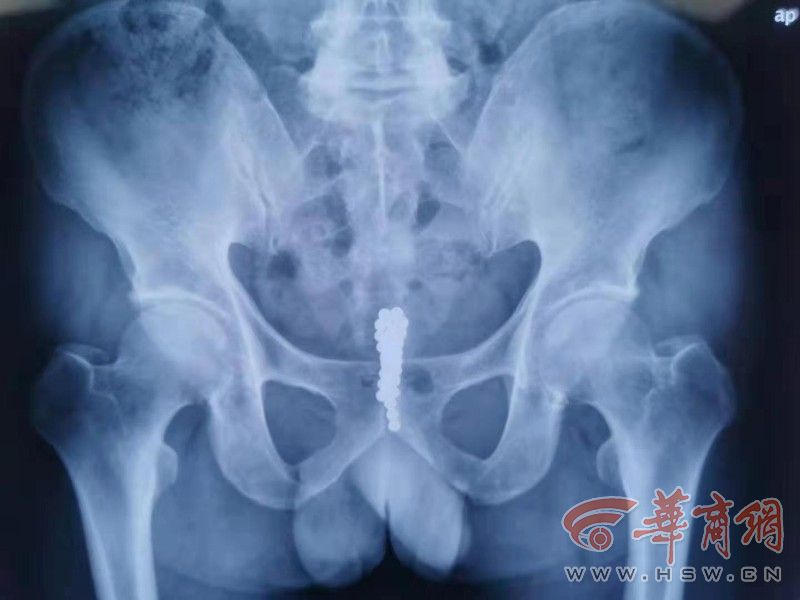

男子尿道塞入28颗磁力球 称是睡梦中无意识行为

华商报记者 卿荣波10月29日,医生提醒说,从尿道塞异物是非常危险的,"